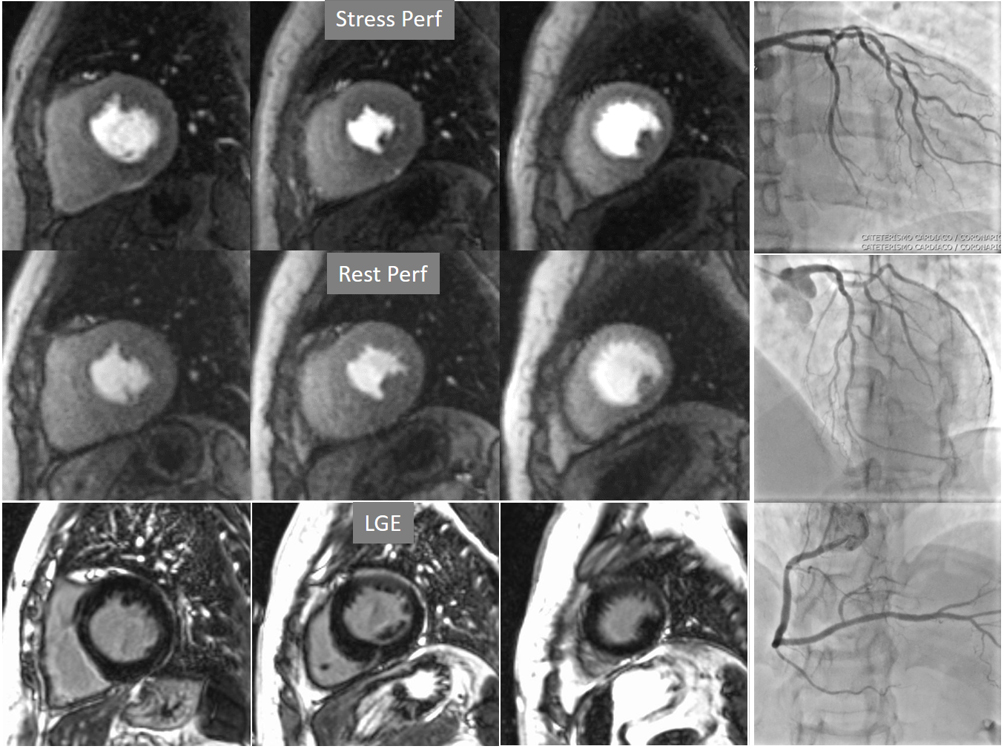

The most immediate and commonest method of analysis is the visual detection of a distinctive deficient increase in signal intensity of a region of the left ventricular myocardium during the first passage of a CA bolus under vasodilatory conditions lasting for at least 3 consecutive frames of the sequence. This perfusion defect should not be present at rest and should not correspond to an area of previous MI. The detection of such a defect is assumed to be due to a reduction in CFR of this territory which, when attributed to a particular coronary artery [39], allows for the conclusion of the presence of a significant epicardial stenosis in the vessel (Fig. 6).

Fig. 6.Single-vessel perfusion defect. Extensive subendocardial perfusion defect at the antero-septal region (arrow, on the upper left panel) not present at rest, in a region without LGE (lower left panel). Angiography proves this defect to be due to a tight stenosis of the LAD coronary artery (arrow, on the lower right panel).